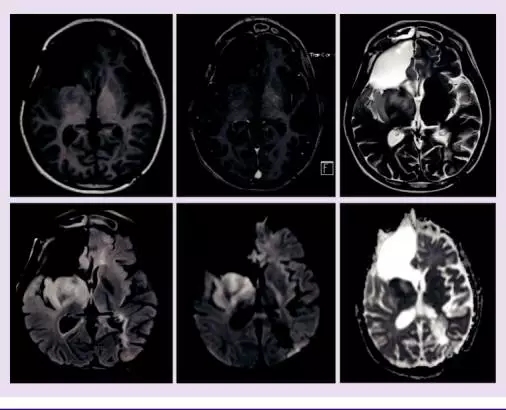

患者在13岁时被诊断为胶质母细胞瘤,在进行手术切除之后,进行了放疗和化疗,但是病情还是进展了。通过MRI 进行了6个月的观察我们可以观察到离散的肿瘤生长,随后,我们开始使用电场疗法进行临床及影像监测7个月,病情稳定。电场疗法起到了预防胶质母细胞瘤复发和抑制其生长的作用,并且在七个月的治疗期间,对13岁的女孩无重大不利影响。我们认为,电场疗法在胶质母细胞瘤的治疗中有潜在价值。

这个13岁的女孩因逐渐恶化的头痛就诊,最初被认为是感冒或过敏。她和父母生活在一起生活,正在读初中,从不抽烟喝酒,母亲家族中有高发结肠癌家族史。在头痛发作一个月后,她的初级保健医生建议她做进一步神经学检查,图像上看,右侧幕上显示肿瘤存在,MRI发现,两侧区域都出现对比度增强和囊性坏死。她在当地的儿童医院进行了第一次手术切除。